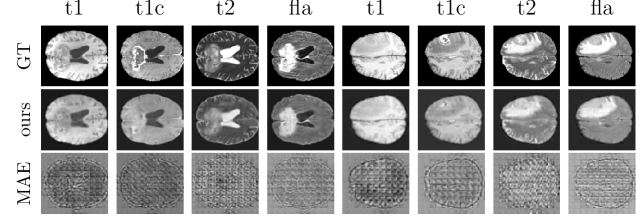

As shown in Table 1 and Figure 2, the model produces anatomically realistic outputs, though some blurring and loss of fine detail remain. In contrast, the vanilla ViT fails to achieve comparable reconstruction quality, even after pretraining.

Refer to caption

Figure 2: Reconstruction of a missing modality. The depicted modality was fully masked (for MAE: replaced with background), and then reconstructed using the remaining inputs.